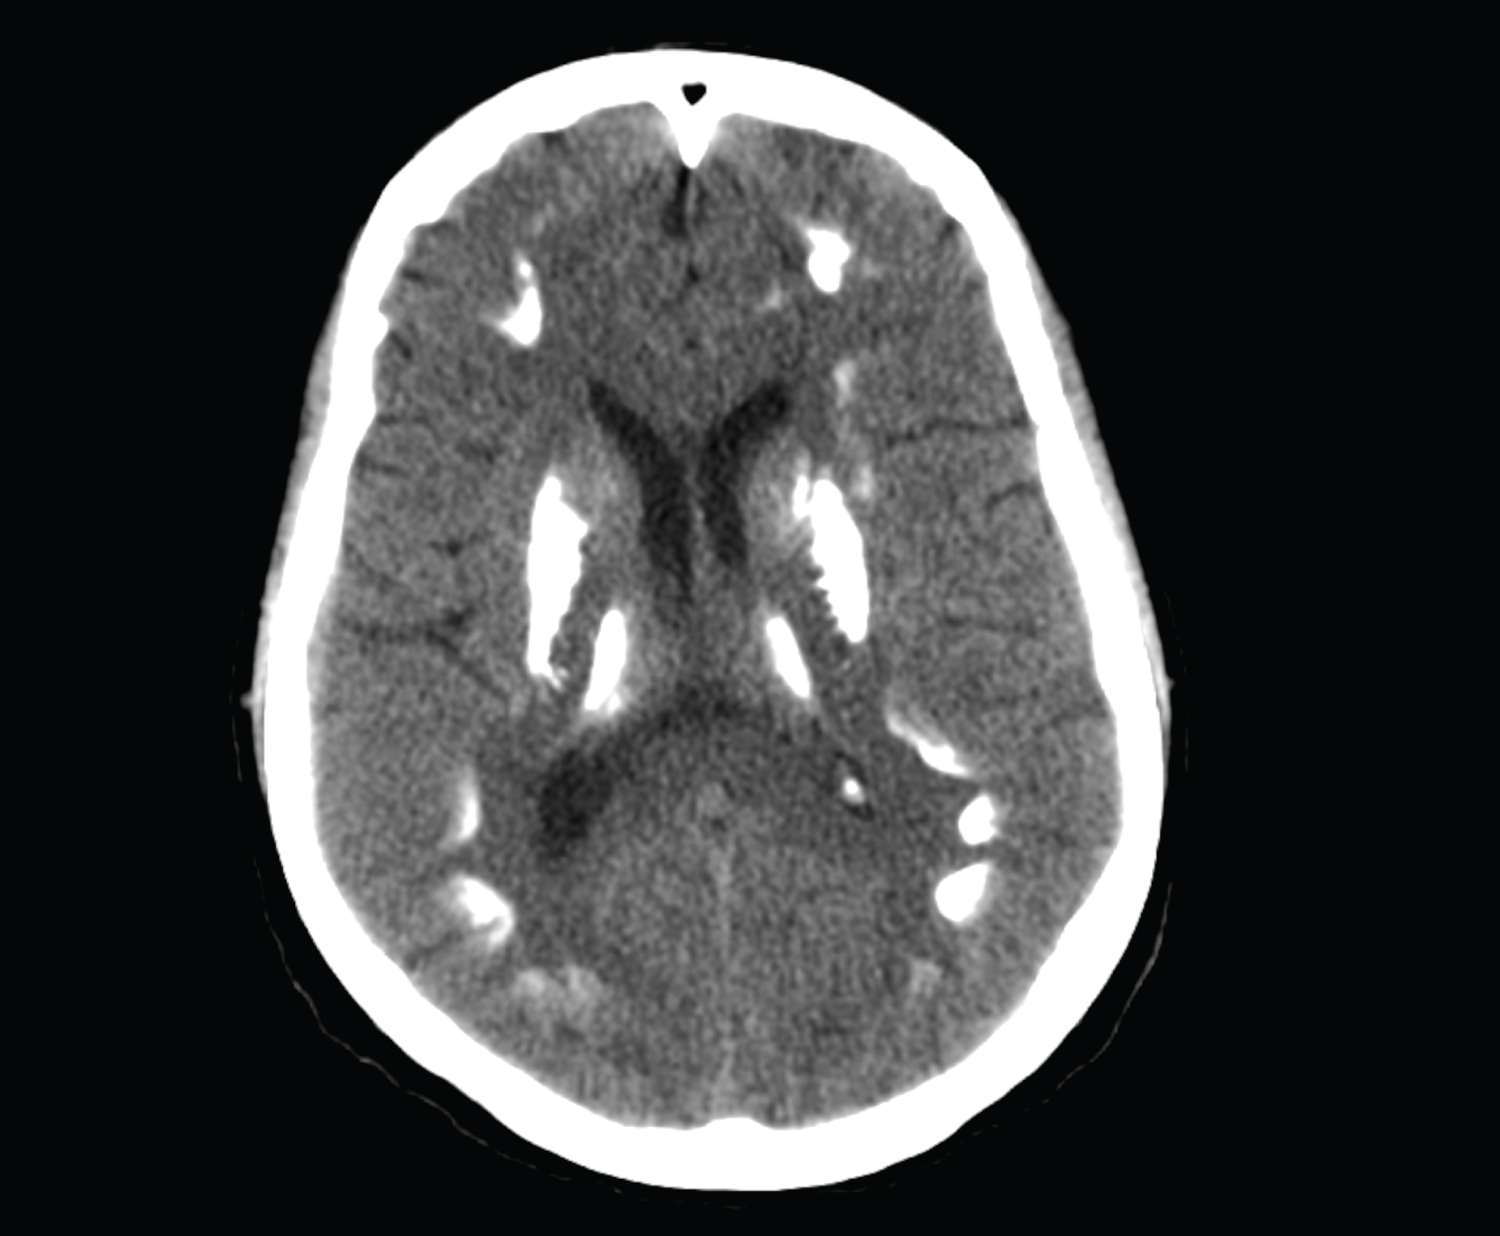

27-year-old female patient who was brought to the Emergency Department of our hospital with the complaints of severe headache and vomiting. Her general condition was moderate, she was conscious, disorientated, and cooperative. Pupils were isochoric, bilateral light reflex was positive, and there was no lateralized motor deficit. Glasgow Coma Score was evaluated as 14 points. Blood pressure was measured to be 130/80 mmHg, pulse was 90/min, respiratory rate was 14/min, and fever measured 36 centigrade degrees. Head CT reported as hyperdense appearance compatible with intraventricular hematoma in both lateral ventricles and at the level of 3rd and 4th ventricle (Figure 1). Disseminated subarachnoid hemorrhage and additionally widespread calcification across bilateral basal ganglia, thalamus, and subcorticalwhite matter detected. Patient first taken to the OR to place an external ventricular drainage (EVD) catheter (Figure 2). Then DSA performed which revealed saccular aneurysmatic filling with 5*3 millimeters in diameter at the apex of the right Internal Carotid Artery just before theM1 segment of Middle Cerebral Artery. Endovascular coil placement was performed for aneurysm treatment (Figure 3). Then patient was taken to the neurosurgery intensive care unit for post-operative (PO) close follow-up. On the PO-5th day, she was taken to the in-patient floor due to wellness in her general condition. Control angiography showed successful closure of the aneurysm (Figure 4). Patient followed up three days with EVD closed as the clarification of the color of the cerebrospinal fluid in the catheter and resorption of the intraventricular hemorrhage in the control tomography observed (Figure 5). As no changes seen in the clinical status EVD catheter removed and patient discharged to home on the PO-12th day.

Figure 1: In the brain tomography of the patient who applied to the emergency department with the complaint of headache, there is a hyperdense appearance compatible with intraventricular hematoma in both lateral ventricles and at the level of the 3rd and 4th ventricles. View Figure 1